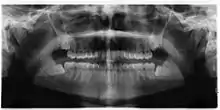

Impacted wisdom teeth

Other namesImpacted third molars

Impacted third molar

3D CT of an impacted wisdom tooth adjacent the inferior alveolar nerve prior to removal of wisdom tooth

Impacted wisdom teeth is a condition where the third molars (wisdom teeth) are prevented from erupting into the mouth.[1] This can be caused by a physical barrier, such as other teeth, or when the tooth is angled away from a vertical position.[2] Completely unerupted wisdom teeth usually result in no symptoms, although they can sometimes develop cysts or neoplasms. Partially erupted wisdom teeth or wisdom teeth that are not erupted but are exposed to oral bacteria through deep periodontal pocket, can develop cavities or pericoronitis. Removal of impacted wisdom teeth is advised for the future prevention of or in the current presence of certain pathologies, such as caries (dental decay), periodontal disease or cysts. Prophylactic (preventative) extraction of wisdom teeth is preferred to be done at a younger age (middle to late teenage years) to take advantage of incomplete root development, which is associated with an easier surgical procedure and less probability of complications.[3]

Impacted wisdom teeth are classified by their direction of impaction, their depth compared to the biting surface of adjacent teeth and the amount of the tooth's crown that extends through gum tissue or bone. Impacted wisdom teeth can also be classified by the presence or absence of symptoms and disease. Screening for the presence of wisdom teeth often begins in late adolescence when a partially developed tooth may become impacted. Screening commonly includes a clinical examination as well as x-rays such as panoramic radiographs.